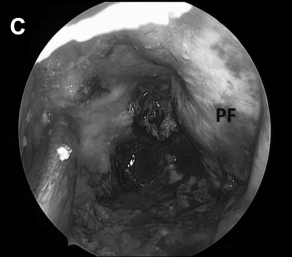

▼图示:(A) Binostril 和 (B) 使用有角度器械的单鼻孔入路。旋转轴与吸力角度相结合,导致手指的小动作在曝光深度上被放大,并允许 360 度范围。当用拇指和中指和无名指控制时,吸力还可以沿前后方向移动。

图示为筷子技术,A图表示筷子夹在拇指和手指之间。B图表示内窥镜和抽吸(或其他器械)可以类似地保持在外科医生的非主导手中。旋转轴与抽吸尖端的远端角度结合可以将小手指运动转换成暴露深度中的360度范围。